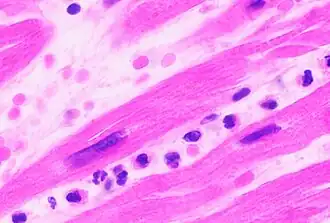

Neutrophils with segmented nuclei surrounded by erythrocytes and platelets. Intra-cellular granules are visible in the cytoplasm (Giemsa stained).

The name neutrophil derives from staining characteristics on hematoxylin and eosin (H&E) histological or cytological preparations. Whereas basophilic white blood cells stain dark blue and eosinophilic white blood cells stain bright red, neutrophils stain a neutral pink. Normally, neutrophils contain a nucleus divided into 2–5 lobes.[7]

With the eosinophil and the basophil, they form the class of polymorphonuclear cells, named for the nucleus' multilobulated shape (as compared to lymphocytes and monocytes, the other types of white cells). The nucleus has a characteristic lobed appearance, the separate lobes connected by chromatin. The nucleolus disappears as the neutrophil matures, which is something that happens in only a few other types of nucleated cells.[16]: 168  Up to 17% of female human neutrophil nuclei have a drumstick-shaped appendage which contains the inactivated X chromosome.[17] In the cytoplasm, the Golgi apparatus is small, mitochondria and ribosomes are sparse, and the rough endoplasmic reticulum is absent.[16]: 170  The cytoplasm also contains about 200 granules, of which a third are azurophilic.[16]: 170